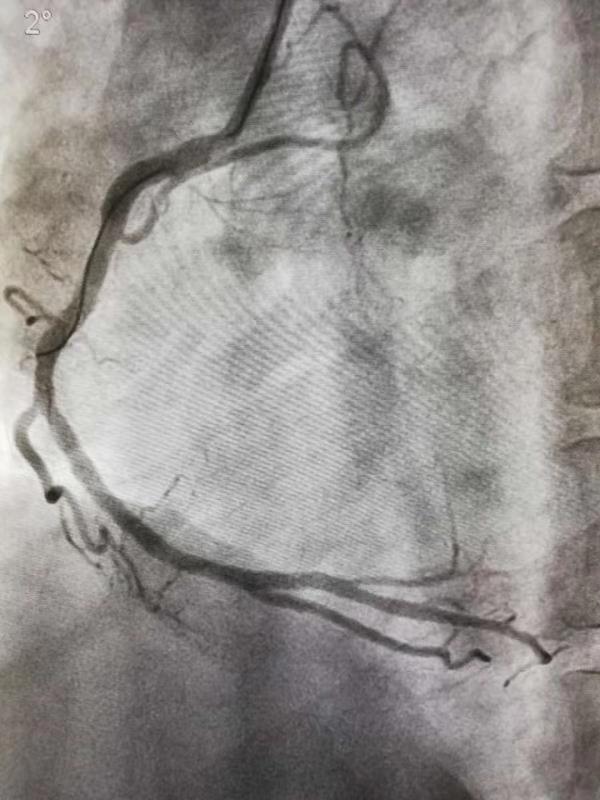

12月19日6:24分,35岁的小伙姚先生因突发胸痛半小时被送入我院急诊就诊,胸痛中心医师迅速急查心电图,发现其下壁急性心肌梗死。经过沟通,家属同意手术。立即消毒、穿刺右侧桡动脉,送入导管行冠脉造影,发现右冠中远段90%狭窄,可见附壁血栓。植入一枚支架,复查造影狭窄消失,手术成功,术后安返CCU。